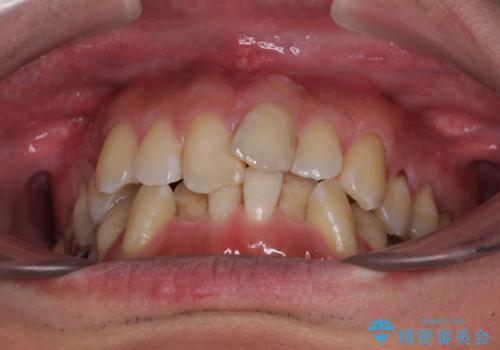

- 前歯のデコボコを気にして来院された患者様です。

下顎前歯のデコボコが特に強く、治療を早く終えることを考えるとワイヤー装置がお勧めですが、ワイヤー装置の異物感は避けたいのでインビザラインを希望されていました。

下顎にワイヤー装置を装着し、暫くしたところでやはりインビザラインにて矯正治療をしたいとのことで、インビザラインに切り替えました。

短い期間でしたがワイヤー装置を使用したことでデコボコが解消されたため、インビザラインの比較的短い期間で矯正治療を行うことができました。